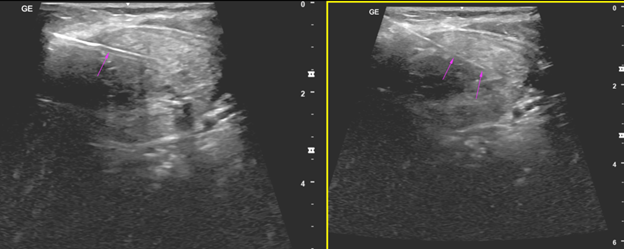

USG-guided biopsy of the lesion was done which was seen in the left lobe of the thyroid. Patient neck was extended with a pillow placed under the upper dorsal region. Easy biopsy and the samples were sent to HPE.

Needle used: 17G introducer needle. 18 G biopsy gun.